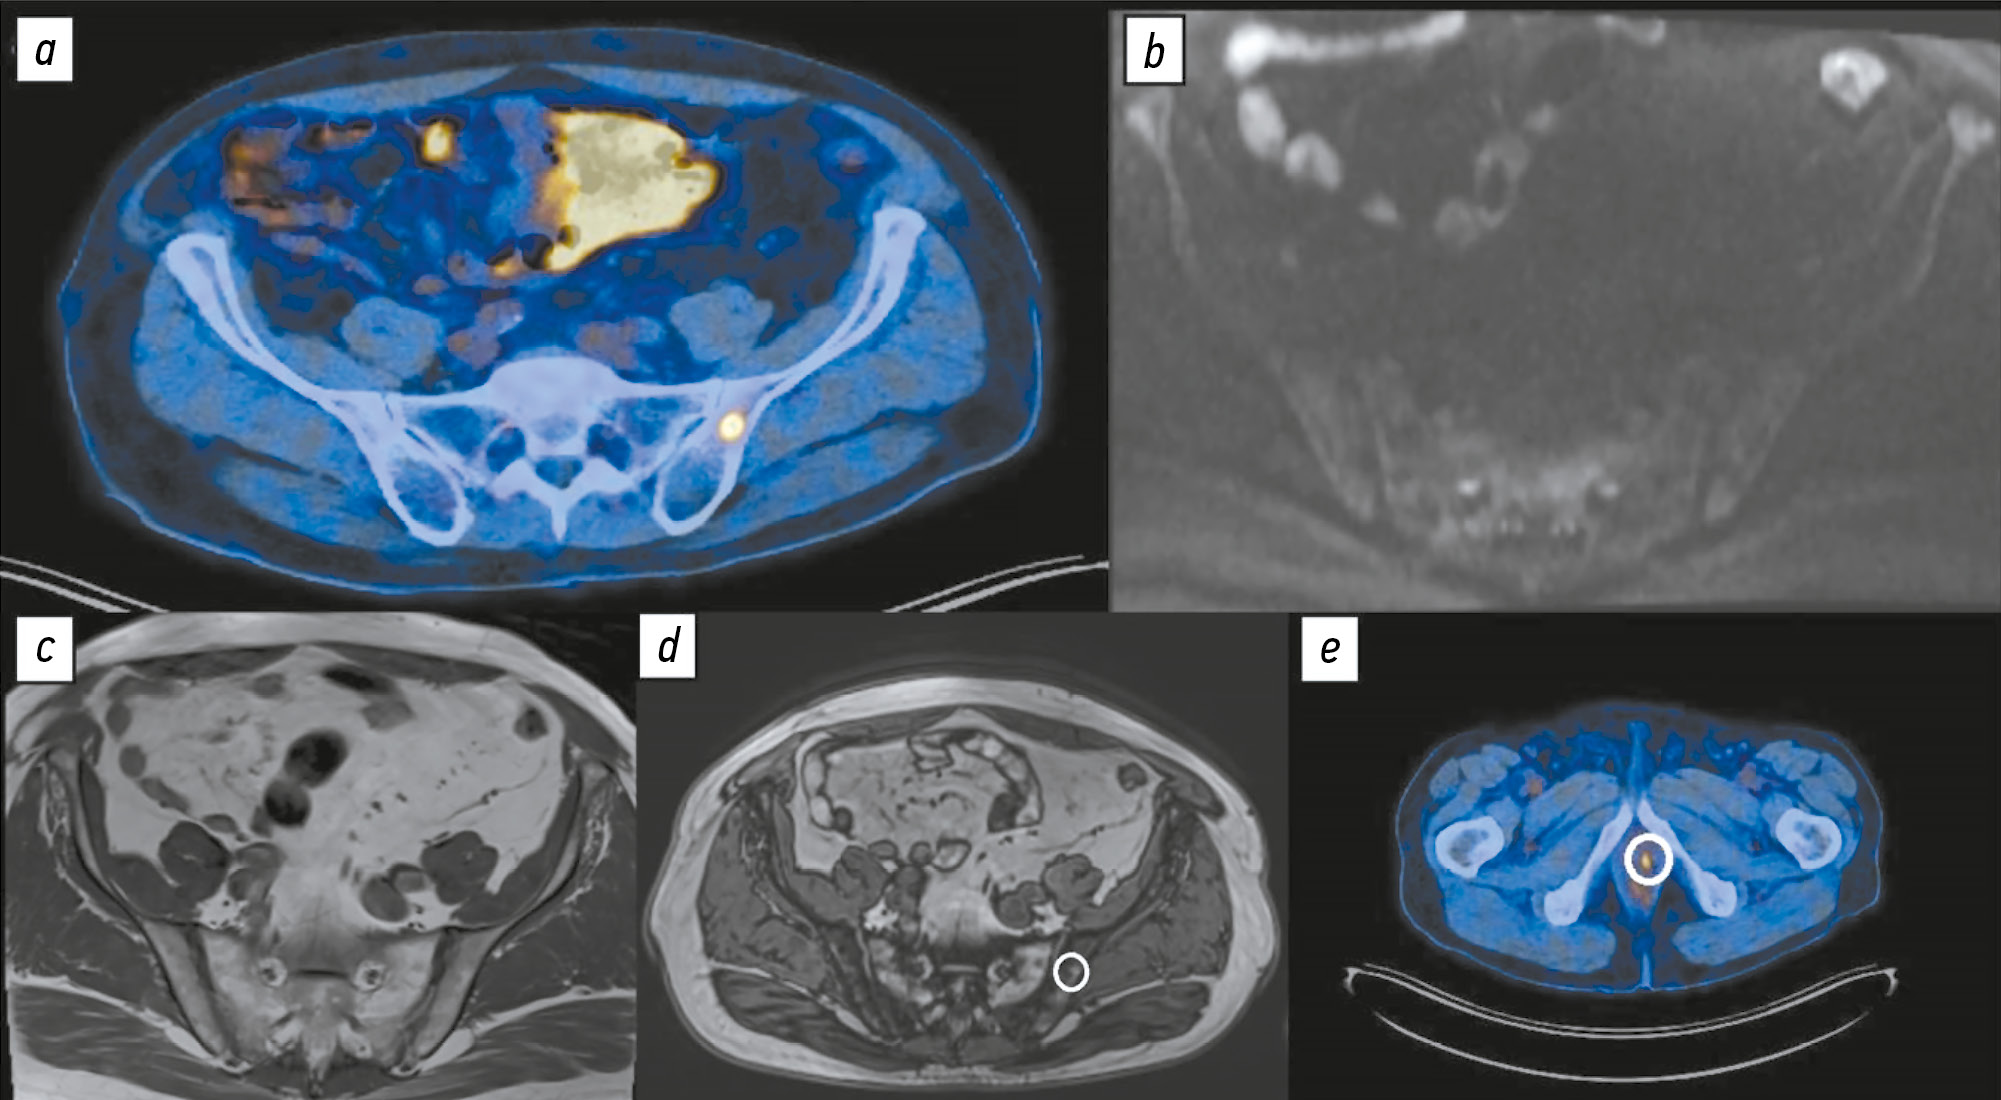

Comparison of the diagnostic accuracy of whole-body diffusion-weighted imaging and 18F-prostate-specific membrane antigen-1007 positron emission tomography combined with computed tomography for detecting bone metastases in prostate cancer

Аннотация

BACKGROUND: The increasing availability of 18F-prostate-specific membrane antigen-1007 (18F-PSMA-1007) for prostate cancer staging highlighted its advantages, particularly its higher spatial resolution compared to analogs. Moreover, accumulating scientific data indicate an increase in false-positive findings, predominantly in bones, which may lead to unwarranted upstaging of the disease. Diffusion-weighted imaging may be used for the early detection of bone metastases.

AIM: This study aimed to assess and compare the diagnostic accuracy of whole-body 18F-PSMA-1007 positron emission tomography combined with computed tomography and whole-body and pelvic bone diffusion-weighted imaging in patients with prostate cancer.

METHODS: A retrospective single-center selective study was conducted. The imaging results of 119 patients with prostate cancer were divided into two groups: group 1 comprised 40 pairs of 18F-PSMA-1007 positron emission tomography combined with computed tomography and whole-body diffusion-weighted magnetic resonance imaging scans, and group 2 included 79 pairs of similar studies, with magnetic resonance imaging performed only for the pelvic bones. The diagnostic studies were performed at an inter-study interval ≤14 days. The metastatic bone lesions detected in different anatomical regions was counted using data from 18F-PSMA-1007 positron emission tomography combined with computed tomography and magnetic resonance imaging. Lesions were considered true positives if confirmed by additional magnetic resonance imaging pulse sequences and/or follow-up observation.

RESULTS: Whole-body diffusion-weighted imaging demonstrated higher specificity (58.1%) for detecting bone metastases than 18F-PSMA-1007 positron emission tomography combined with computed tomography (51.06%). However, its sensitivity was lower: 93.22% versus 97.55%.

CONCLUSION: Despite its advantages, 18F-PSMA-1007 positron emission tomography combined with computed tomography shows a high rate of false-positive bone findings. These are most commonly noted in the ribs, vertebrae, and pelvic bones. Suspicious bone lesions should be further evaluated to avoid unjustified disease upstaging. Thus, whole-body magnetic resonance imaging with diffusion-weighted sequences and selective fat signal suppression can be used.

239-250